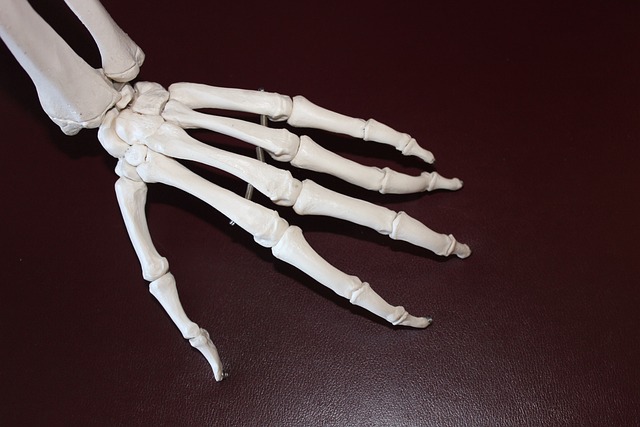

- X-레이: 슬개골과 대퇴골 사이의 정렬 상태를 평가하고, 뼈의 구조적 문제가 있는지 확인합니다. 그러나 X-레이는 연골 자체는 보여주지 않습니다.